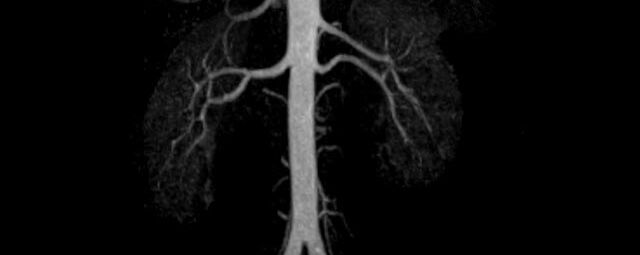

MR-Angiografie (MRA)

• MR-Angiografie ohne Kontrastmittel

• Time of Flight (TOF)-Angiographie

Je nach Fragestellung und Körperregion Gefäßdarstellung ohne Kontrastmittel bei Kontrastmittelunverträglichkeit oder terminaler Niereninsuffizienz möglich.

• MR-Angiographie mit Kontrastmittel

• Erfassung arterieller und venöser Gefäße/Bypässe aller Körperregionen mit 3D-Rekonstruktion

• Bauchgefäße

• Erfassung und Verlaufskontrolle bei arteriellen Aneurysmen (Aussackungen der Arterien), vor allem der Bauchaorta

• Darstellung von Gefäßengen an Nierenarterien, Baucharterien und Becken-/Beinarterien